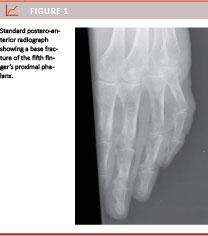

Plain radiographs (postero-anterior (PA) and lateral views) were used to identify the fracture (Figure 1). Fracture reduction was performed under local anaesthetics. The fifth digit was fixed to the fourth (Figure 2) using 1/2” Buddy-Loops (3-Point Products) or 1/2” surgical tape (3M Micropore) and mobilisation of all finger joints was initiated immediately. Patients were examined in our outpatient clinic one and two weeks after the trauma. Radiographs were repeated only in the event that the clinical examination showed malalignment. Patients who were reluctant to mobilise their finger were referred to a hand therapist.